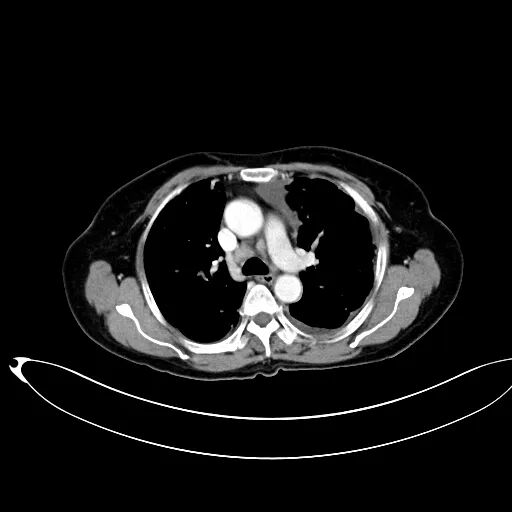

患者骨科手术后呼吸困难,急诊肺动脉CTA检查,增强CT未见充盈缺损,肺血栓形成目前不考虑。但是患者为什么出现呼吸困难,脂肪栓塞?看看CT平扫,有什么发现?乍一看,还以为是纵隔淋巴结或血管钙化,说不定还会随口给家属一句“是钙化,不用处理,没事”。结合病史,仔细一看,原来是奇葩骨水泥肺栓塞。事可大了!双肺多发的骨水泥肺栓塞。这种情况下,看增强CT,造影剂反而会掩盖肺栓塞。胸片:胸片也能诊断骨水泥肺栓塞。术前几乎都要常规做胸片,术后胸片发现新增的条状、树枝状高密度阴影,结合临床表现,也可诊断骨水泥肺栓塞。超声:心脏彩超可发现心脏内的骨水泥栓子,床旁超声也可搞定,还可以同时评价心脏功能。

肺动脉骨水泥沉积后位置、形态一般不发生变化;肺动脉走行区分支状高密度影(CT值>500HU);管腔内:高密度影直径小于近端肺动脉管腔直径;术前片对比新发实验室检查:D-二聚体、血气分析血氧饱和度、肺动脉血流动力学纤细的条纹状影,表现为肺纹理内细线纹状高密度影多位于肺野外围小动脉,分布较均匀,范围较广;节段性柱状、条状影,表现为肺纹理内呈不连续细柱状条状、枯树枝样高密度影,为肺动脉节段性完全或不完全充盈,也见于较细肺动脉分支;多发斑点状密度,肺野外围纹理内多发点状高密度影为少量骨水泥呈斑点状散在分布于小动脉所致肺栓塞并椎旁静脉渗漏。

明确经皮椎体成形术病史,术中不一定出现骨水泥渗出,可迟发临床症状,无症状至胸痛、呼吸困难、急性呼吸窘迫综合征甚至死亡。PMMA材料射线衰减强,X线平片即可发现病灶,CT平扫可进一步准确定位病灶,CTA不是必须。